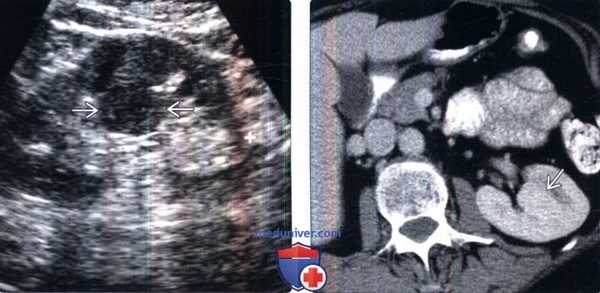

(Слева) УЗИ, продольная плоскость сканирования: гипоэхогенное «объемное образование» в центре, которое выступает в почечную лоханку.

(Справа) КТ с контрастированием, аксиальная проекция: у этого же пациента установлено, что «объемное образование» — это нормальное корковое вещество почки, которое инвагинирует в почечную лоханку между чашечками верхнего полюса и меж полюсной областью почки. Обратите внимание на нормальный внешний контур почки. Бертиниевы колонны чаще всего выявляют с одной стороны и слева, как в данном случае: в 18% случаев они могут быть двусторонними.